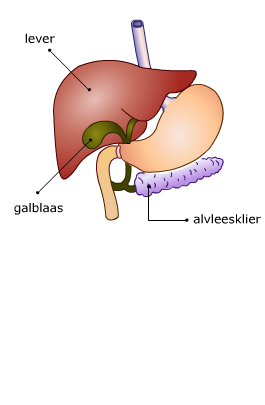

Alvleesklier en galblaas

De alvleesklier ligt in de buikholte achter de maag. De alvleesklier is 12 tot 15 cm lang en weegt zo'n 80 gram.

De alvleesklier ligt in de buikholte achter de maag. De alvleesklier is 12 tot 15 cm lang en weegt zo'n 80 gram.

De alvleesklier scheidt verteringsappen af. Via een afvoerkanaal gaan deze verteringssappen naar de twaalfvingerige darm.

In de galblaas wordt gal opgeslagen.

Gal is een dikke, geelgroenige vloeistof die door de lever wordt uitgescheiden. Gal wordt afgegeven aan de darm als er vet voedsel door de twaalfvingerige darm gaat. Gal verdeelt vet in kleinere bolletjes, daardoor kan het vet makkelijker verteerd worden.